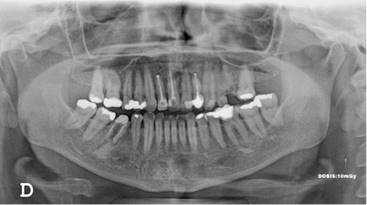

Los resultados mostraron que en el 48 % de la población se encontró algún hallazgo relacionado con la pulpa dental, con frecuencias similares entre hombres y mujeres, siendo el tratamiento endodóntico el más frecuentemente encontrado (Tabla 1, Fig. 1). El rango del número de endodoncias por radiografía fue de 1 a 18. El 86,4 % de las radiografías presentaron de 1-5 endodoncias, 11,4 % de 6-10 y el 2,2 % de 11-18. La presencia de zona radiolúcida periapical seguida por la reabsorción (Fig. 2), fueron los siguientes hallazgos más frecuentes. (Tabla 1)

Los otros hallazgos analizados (Fig. 3) se presentaron en muy baja frecuencia. Para ninguno de los casos, se encontraron diferencias estadísticamente significativas entre hombres y mujeres.